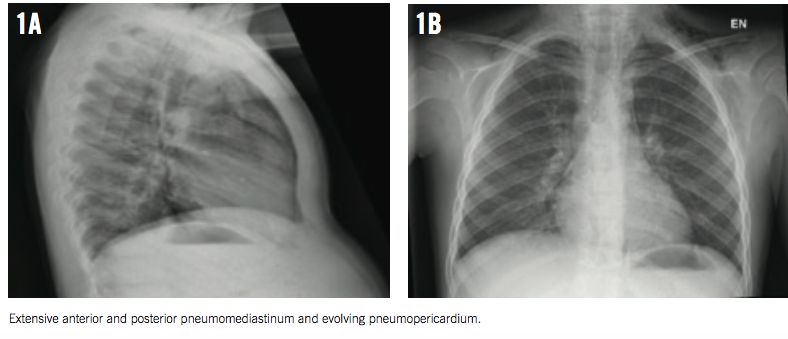

On auscultation over the chest, a systolic crunching sound was heard, with accentuation during inspiration (Hamman sign). The rest of the boy’s physical examination results were unremarkable. However, a bedside chest radiograph revealed pneumomediastinum (Figures 1A and 1B).

For better delineation of the extent of air dissection, a computed tomography (CT) scan of the chest was obtained, which revealed extensive pneumomediastinum, small bilateral pneumothoraces, pneumopericardium, and pneumoretroperitoneum mostly on the left (Figures 2 and 3).